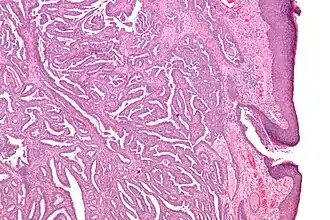

| Micrografia de um adenoma do mamilo. | |

Adenoma do mamilo é um tumor da mama benigno e raro. Trata-se de um papiloma intraductal que surge nos ductos lactíferos do mamilo.[1] São mais comuns nas mulheres entre os 30 e 40 anos,[2] embora possam também ocorrer em homens.[3] Podem ocorrer em qualquer idade, incluindo na velhice, adolescência[4] e infância.[5] Podem ser detectados por palpação na forma de um nódulo por baixo do mamilo ou da aréola e chamar à atenção devido a dor no mamilo, ulceração, inchaço ou corrimento.[2]